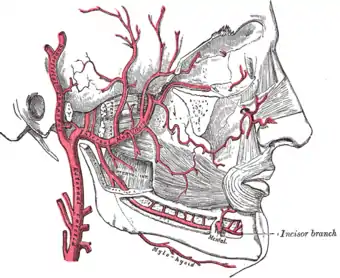

L'artère maxillaire ou l'artère maxillaire interne en ancienne nomenclature[1] (Arteria maxillaris ou Arteria maxillaris interna en latin) est une des deux branches terminales de l'artère carotide externe. Elle participe entre autres à la vascularisation de la partie inférieure de la face, de l'oreille ainsi que de certaines structures intracrâniennes.

L'artère maxillaire est la plus importante des deux branches terminales de la carotide externe, l'artère temporale superficielle étant la plus petite. Elle naît dans la glande parotide, en arrière du col de la mandibule et se dirige vers l'avant, perpendiculairement à la carotide externe. Dans de rares cas, l'artère maxillaire provient de l'artère faciale[2].

L'artère maxillaire est classiquement divisée en trois segments : un premier segment mandibulaire, un deuxième segment ptérygoïdien et un troisième segment ptérygo-palatin[3]

Après avoir irrigué une partie de la glande parotide, l'artère maxillaire quitte la loge parotidienne par la boutonnière rétro-condylienne de Juvara, en passant entre le ligament sphéno-mandibulaire médialement et le col de la mandibule latéralement[4]. Elle entre dans la fosse infra-temporale, accompagnée par le nerf auriculo-temporal. L'artère maxillaire croise ensuite le nerf alvéolaire inférieur avant d'atteindre le muscle ptérygoïdien latéral. Elle donne à ce niveau cinq collatérales :

- L'artère alvéolaire inférieure (anciennement appelée artère dentaire inférieure[1]) est une branche descendante de l'artère maxillaire. Elle se dirige vers le bas, accompagnée par le nerf alvéolaire inférieur. Juste avant de pénétrer dans le canal alvéolaire inférieur par le foramen mandibulaire elle donne une branche, l'artère mylo-hyoïdienne, qui descend à la face interne de la mandibule au niveau du sillon mylo-hyoïdien pour vasculariser le muscle du même nom. L'artère alvéolaire inférieure poursuit ensuite son trajet dans le canal alvéolaire et se divise en une branche mentonnière passant par le foramen mentonnier pour vasculariser les téguments du menton, et une branche incisive qui poursuit son trajet et s'anastomose avec l'artère contro-latérale[3]. Elle permet la vascularisation des dents inférieures via des rameaux dentaires[6].

Au niveau du deuxième segment l'artère maxillaire, qui devient assez flexueuse, est satellite du muscle ptérygoïdien latéral. Elle peut passer soit médialement, entre les deux muscles ptérygoïdiens, soit latéralement, entre le ptérygoïdien latéral et le muscle temporal[6]. La variante externe semble être un peu plus fréquente que la variante interne[9],[10]. Dans sa variante superficielle, l'artère maxillaire contourne le bord inférieur du muscle ptérygoïdien latéral pour passer à sa face externe. Elle croise le nerf buccal, issu de la division antérieur du nerf mandibulaire. Dans sa variante profonde, l'artère maxillaire longe la face médiale du muscle ptérygoïdien latéral et se trouve donc dans l'espace interptérygoïdien. Sur son trajet elle croise les nerfs alvéolaire inférieur et lingual au niveau de la réunion avec la corde du tympan[6]. Elle passe ensuite entre les deux chefs du muscle ptérygoïdien latéral pour se retrouver à sa face externe. Le deuxième segment de l'artère maxillaire donne plusieurs collatérales :

Au niveau du troisième segment, l'artère maxillaire décrit une courbe à convexité antérieure qui s'appuie sur la tubérosité maxillaire et entre dans la fosse ptérygo-palatine via la fissure ptérygo-maxillaire[13]. Elle s'engage ensuite dans le foramen sphéno-palatin et devient alors l'artère sphéno-palatine. Le segment ptérygo-palatin de l'artère maxillaire compte cinq collatérales :